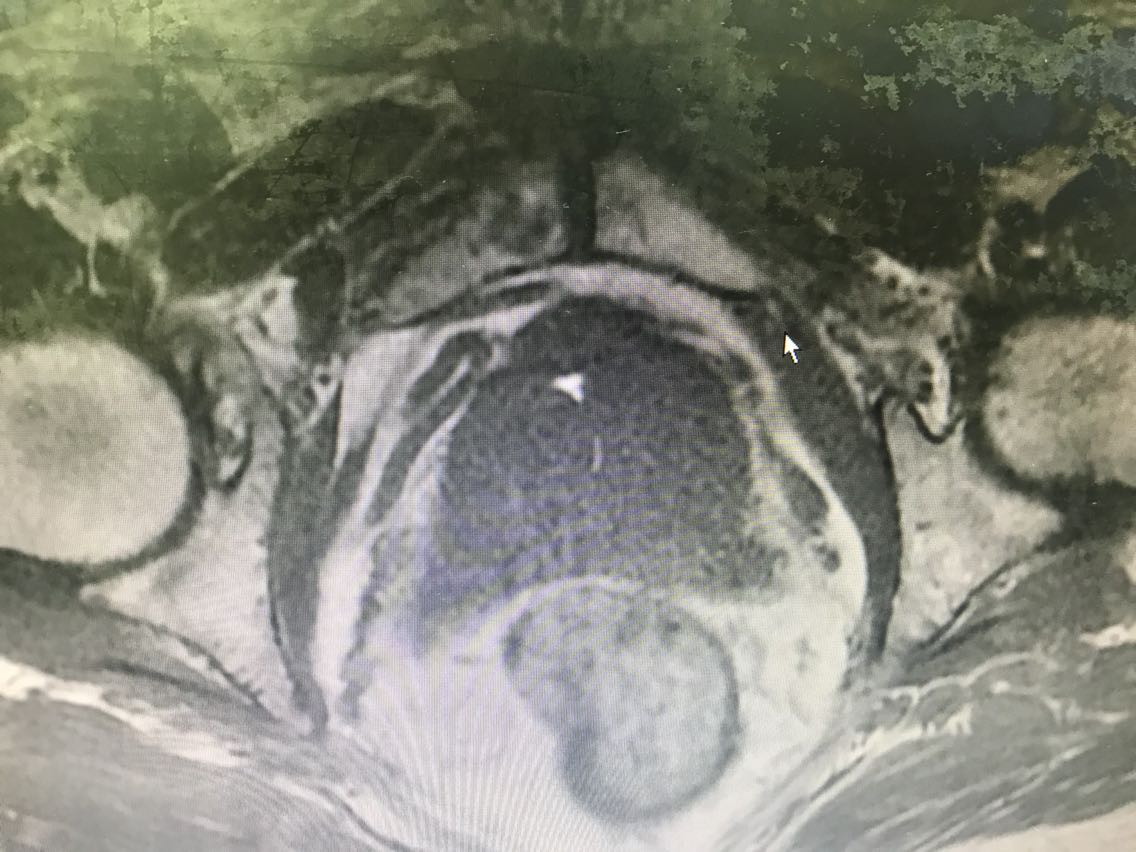

患者男性,77岁。 主诉:血尿7+月 现病史:入院前7+月,患者出现血尿,于外院体检查示PSA升高(10.62),服药血尿控制(具体药物不详),无尿频、尿急、下腹疼痛等不适,为求进一步诊治于我院门诊就诊,查前列腺MRI:前列腺尖部右侧中央带结节及9-10点结节,多系前列腺癌。门诊行前列腺穿刺活检示:编号1、2、3、4、5、6查见前列腺腺癌,Gleason评分4+3=7分。门诊以“前列腺癌”收入我科。患病来精神、睡眠、食欲可,大小便无异常,体重无明显变化。 既往史无特殊。

查体:腹部平软,无压痛及反跳痛,双肾及输尿管走行区无压痛,肾区无叩痛。直肠指检:前列腺Ⅱ°大,双侧质硬,右侧叶扪及约1cm硬结。 辅助检查: 前列腺MRI(2018-6-14,本院):前列腺尖部右侧中央带结节及9-10点结节,多系前列腺癌,累及右侧外周带 前列腺穿刺活检示(2018-6-28,本院):编号1、2、3、4、5、6查见前列腺腺癌,Gleason评分4+3=7分。